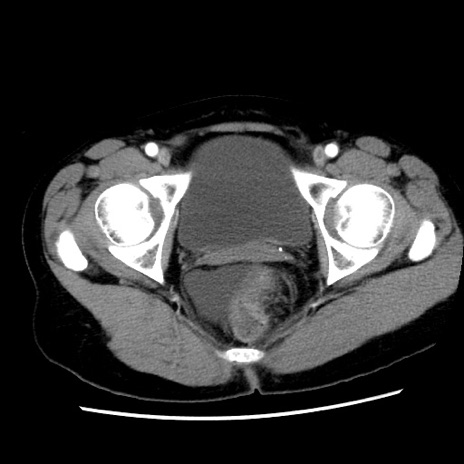

冠状断像

【症例】 50歳代女性

【主訴】 腹痛

【現病歴】前日生レバーを食べた。今朝に排便あり。 昼前に突然発症の腹痛を生じ、当院救急外来を受診した。

【既往歴】 子宮筋腫にてで子宮全摘後

【身体所見】 意識清明、腹部:平坦、軟、下腹部やや左を中心に圧痛・反跳痛あり、筋性防御あり

【データ】WBC 7800、CRP 0.07